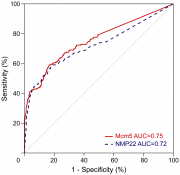

| 11:51, 30 בנובמבר 2017 | CTCL2.png (קובץ) |  |

115 קילו־בייטים | Motyk | 1 | |

| 11:47, 30 בנובמבר 2017 | CTCL1.png (קובץ) |  |

156 קילו־בייטים | Motyk | 1 | |